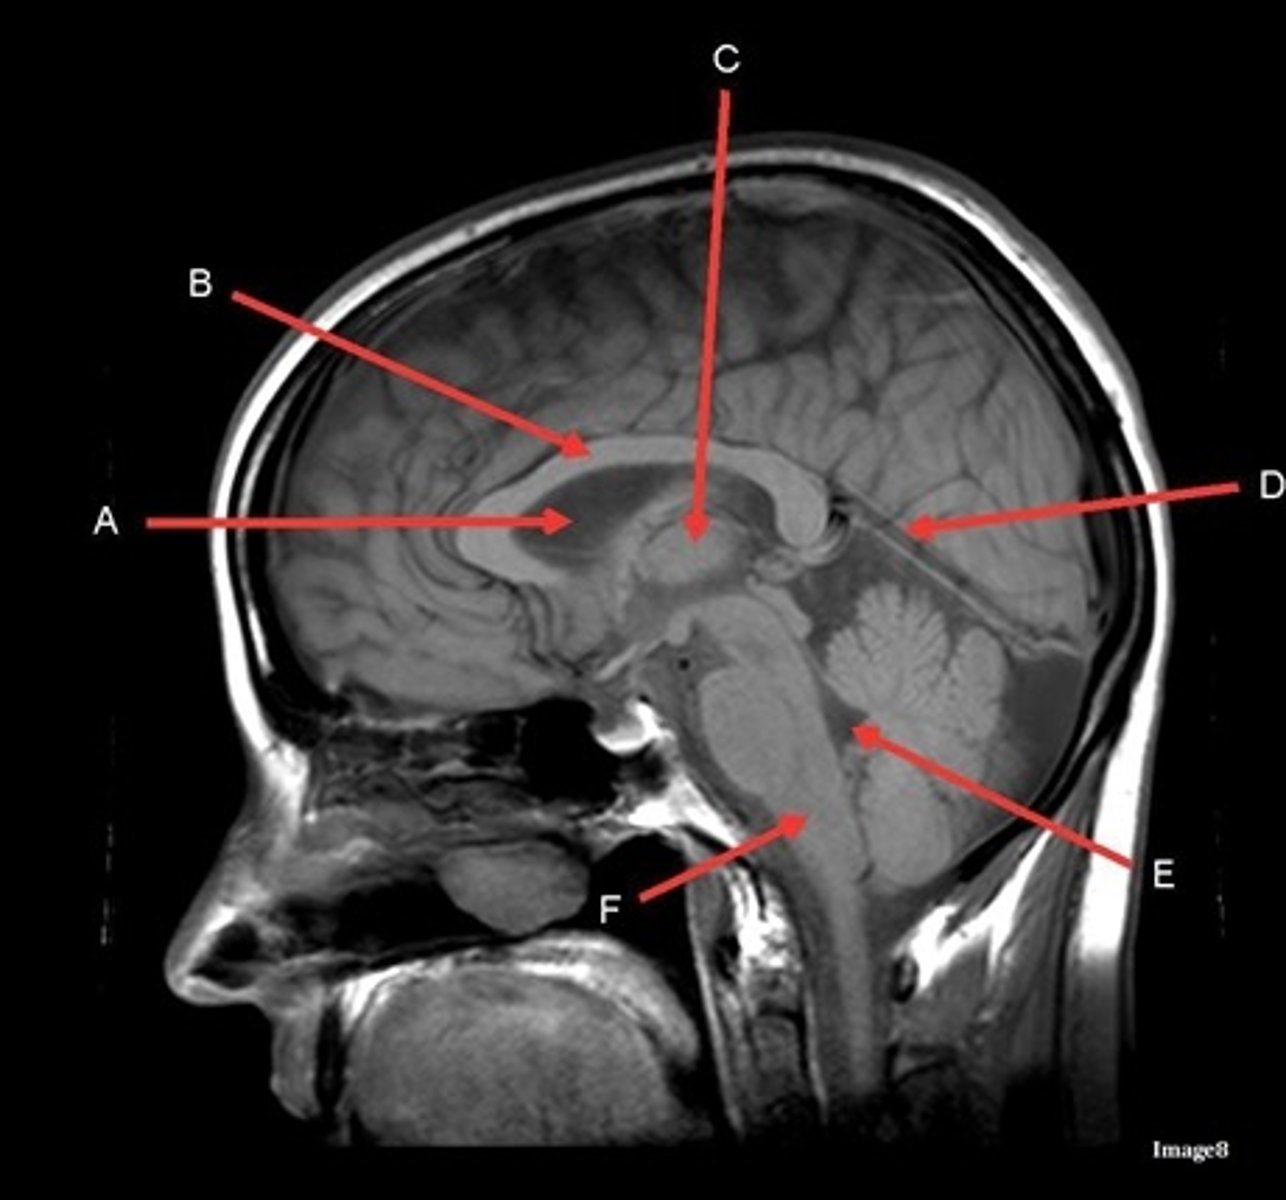

A

lateral ventricle

B

corpus callosum

C

thalamus

D- separates what

tentorium cerebelli- cerebrum (occipital and temporal lobes) from brainstem and cerebellum

E

fourth ventricle

F

medulla oblongata